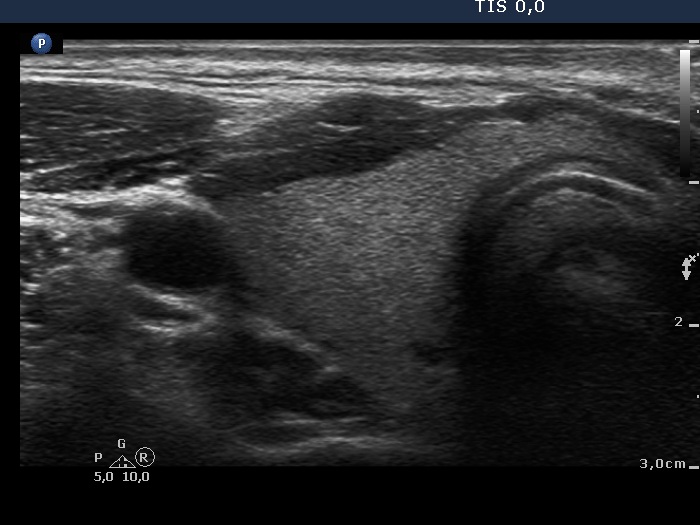

First examination (first row of images)

Clinical data: A 42-year-old woman requested a second opinion. She has been operated on for 3 months. A left lobectomy was performed, and histopathology disclosed a solitary, T2 papillary cancer. No further therapy was suggested.

Palpation: No abnormality.

Hormonal investigation indicated euthyroidism with TSH-level 2.56 mIU/L.

Ultrasonography. The right lobe was echonormal and intact. A hypoechoic, regenerative tissue was found in the isthmus and in the left thyroid bed. A small, deeply hypoechoic lesion was found in the middle of the left thyroid bed with the dimensions of 3x3x4 mm, width, depth and length, respectively.

Suggestion. I agreed with the suggestion of the surgeon. Yearly TSH and ultrasound was advised.